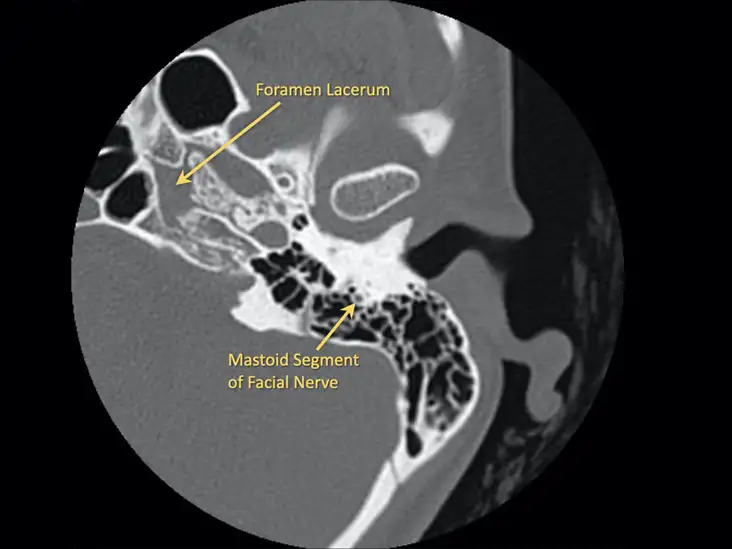

NCCT Temporal bone-axial is Non-Contrast Computed Tomography of Temporal Bone Axial View. It is an imaging scan that focuses on an axial view of the lower skull and the surrounding soft tissues. This scan is recommended for a patient with prolonged ear infections, hearing loss, and middle as well as inner ear diseases.

Doctors prescribe NCCT Temporal Bone-Axial to diagnose both chronic as well as acute swelling, malformation, and tumour formation in the middle ear. It is also used to detect cholesteatoma, congenital or birth defect conditions, and inner ear swelling.

NCCT temporal bone-axial does not use contrast for the procedure. The patient will be advised to lie supine on the bench attached to the scanner for NCCT temporal bone-axial. The bench slides inside the scanner and takes images of the scanning area by using motorised X-rays. The images are used to diagnose the abnormal conditions in the temporal bone-axial.